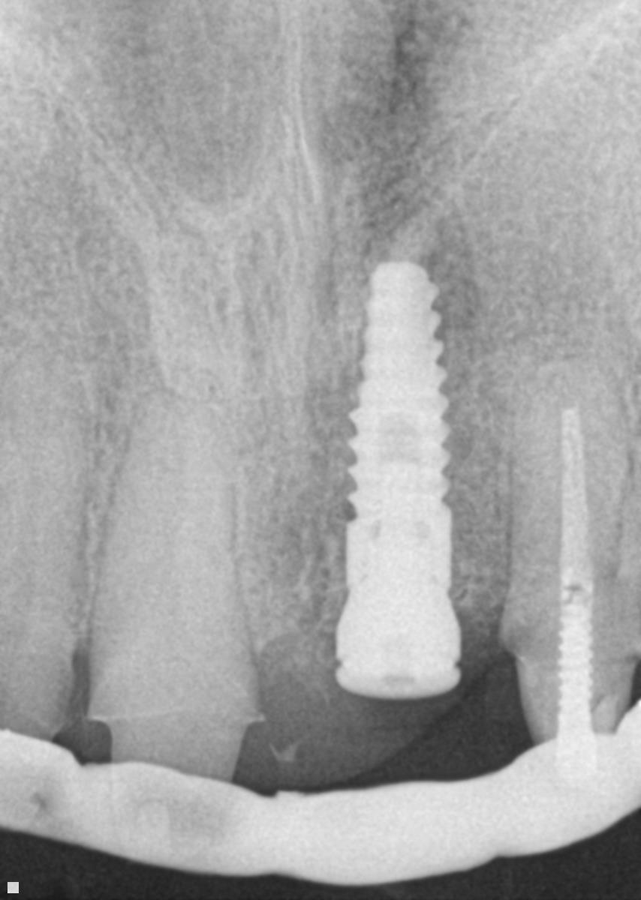

4. After surgery, several X-rays were taken to verify implant placement. Figure 7 shows accuracy to the guided placement for the implant in tooth #12 position (which mirrors the planning stage of Figure 4). Figure 8 shows the implant in tooth #8 position with healing abutment. Figure 9 shows the placement of the implant for tooth #5.

Fig. 7 Fig. 8